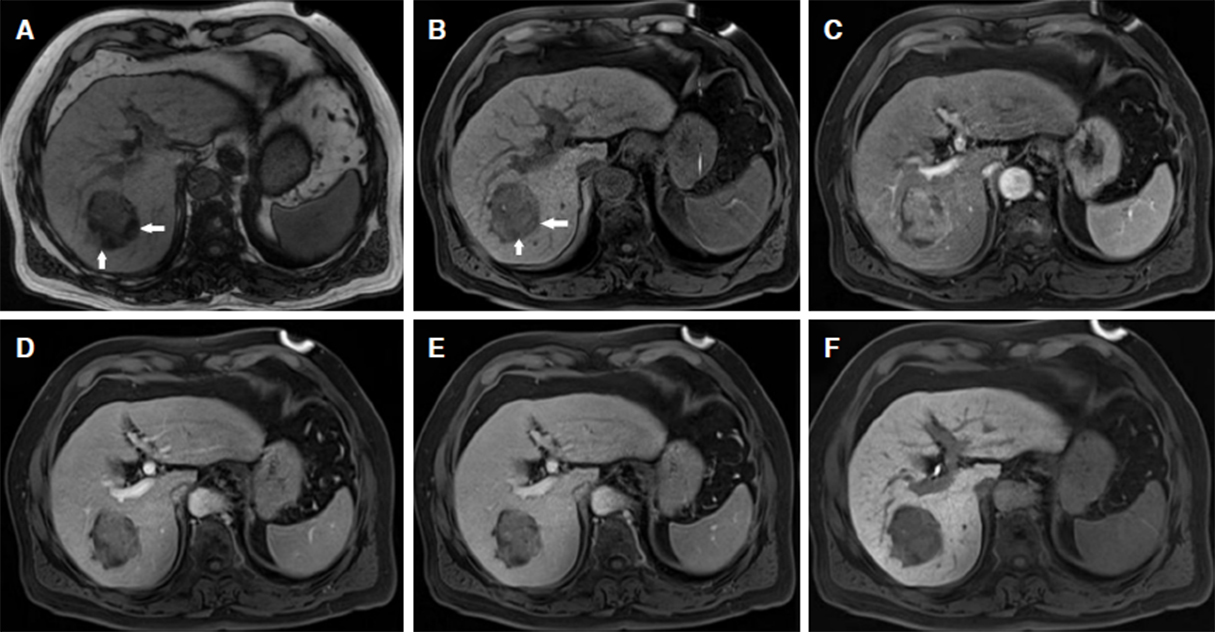

Chemical-shift MRI is the most commonly used technique to monitor the presence of intra-tumoral fat infiltration [Figure 2]. There is a close relationship between intracellular fatty change and MVI in HCC. MVI is more likely to occur in non-containing fatty HCCs, which means intra-tumoral fat infiltration suggests a lower risk for MVI in HCC[79]. Moreover, Kubota et al.[80], reported that macro-vesicular steatosis HCC has a better prognosis with less portal vein invasion and a lower cumulative risk of recurrence than micro-vesicular steatosis HCC. More related research is necessary for detecting intra-tumoral fat infiltration, and predicting the prognosis of HCC with different histopathological characteristics in the early stage of hepatocarcinogenesis, so as to optimize disease management and promote personalized treatment.

Figure 2. A 54-year-old female with hepatocellular carcinoma in segment VII of the liver. The 4.2-cm-sized mass shows focal fatty infiltration (white arrows) on opposed phase image (A) and unenhanced T1-weighted image (B), marked enhancement in arterial phase (C), wash-out appearance in portal venous phase (D) and delay phase (E), and hypo-intensity on 20 min hepatobiliary phase (F)